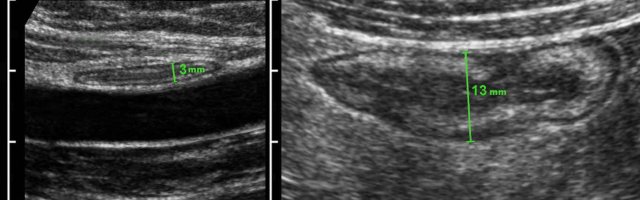

Measuring bowel wall thickness is best and most reproducibly performed during compression, as here in a normal individual (left) and in a patient with Crohn’s disease (right).

Measurements are performed from outer contour of the muscular layer to the opposite side, and then divided by 2, resulting in a wall thickness of 1.5 mm and 6.5 mm for normal resp. Crohn ileum.

See also the section Ultrasound of the GI tract - Normal Anatomy